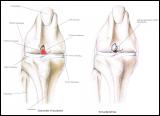

Arthrose im Knie

Der Kreuzbandriß beim Hund ist im Gegensatz zum Menschen in 90 % der Fälle nicht durch einen Unfall verursacht sondern eine Folge von degenerativen Prozessen im Gelenk wie z. B. einer Gelenksarthrose. Begünstigt wird diese Erkrankung z. B. durch Übergewicht. Deshalb geht der betroffene Hund meistens ohne deutlich erkennbare Ursache plötzlich lahm. Beim Neufundländer und Boxer ist eine genetische Anlage bewiesen. Generell gilt aber, dass vor allem ältere kastrierte Hündinnen (> 6-7 J) mit Übergewicht betroffen sind. Die betroffenen Tiere zeigen eine zumeist deutliche Lahmheit am betroffenen Hinterbein. Die Diagnose wird beim Tierarzt durch eine Ganganalyse, den Sitztest, eine umfassende klinische Untersuchung (z. B. Schubladenphänomen, Tibiakompressionstest) und Röntgendiagnostik gestellt. Eine Röntgenuntersuchung in mind. 2 Ebenen ist zwingend erforderlich um weitere Erkrankungen (z.B. eine Arthrose oder eine OCD) festzustellen.